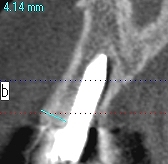

上顎洞への解剖距離が大切です

上顎洞を破ると別の問題が出ます

上顎洞を持ち上げたりします

頬側が骨幅が取れるケースと取れないケースもあります